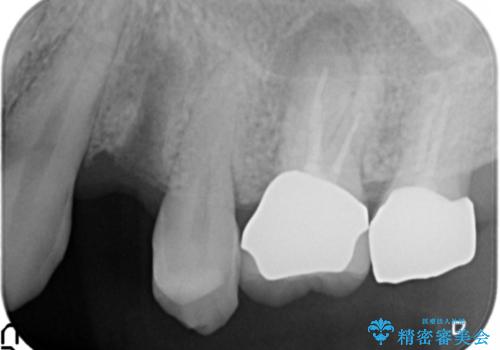

歯がわれた 抜歯してインプラント 50代男性

- 歯ぐきの腫れと痛みを主訴に来院された患者様です。

精査したところ、歯が割れており保存不可能な状態であったためやむなく抜歯しました。

患者様のご希望によりインプラント治療を行いました。